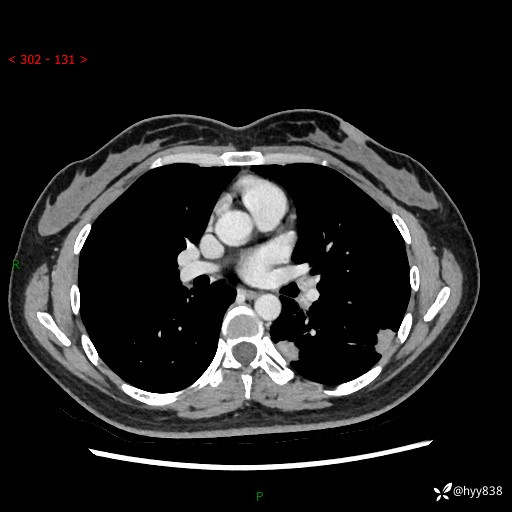

【患者信息】:36岁/女

【主诉】:左侧下胸部阵发性疼痛2周,乏力1周

【现病史及既往史】:患者自诉2周前饮酒后出现左侧下胸部阵发性疼痛,不随呼吸改变,无咳嗽咳痰、头晕头痛、咳血、呼吸困难等不适,于当地第一人民医院查胸部CT提示肺部感染,随后前往我院门诊给予抗感染(左氧氟沙星)治疗1周,自诉胸痛较前好转,感乏力、头晕,偶尔干咳,无咳痰,无发热、畏寒、胸闷、咯血、四肢酸痛、腹泻、腹痛等不适,门诊复查胸部CT提示:左肺下叶感染,病灶较前增加增大,遂以“肺部感染”收入我科。 起病以来,患者精神、饮食、睡眠可,大小便正常,体力体重无明显变化。

【检查】:胸部CT增强(外院平扫)